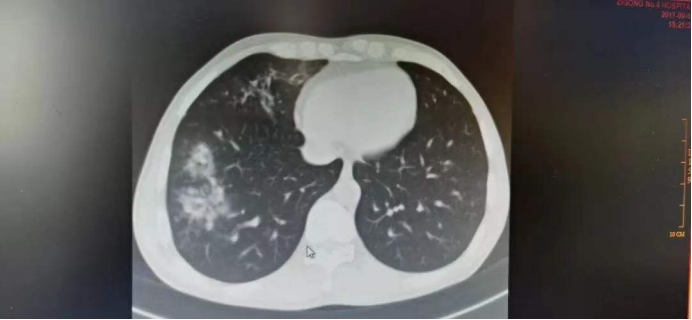

卢某某,男,45岁,因“反复咳嗽4+月,加重伴发热4+天”入院,入院后完善检查,提示肺部感染,病灶呈游走性,予以抗感染治疗效果不佳,后考虑患者系焊工,有金属接触史,考虑“过敏性肺炎”,予以激素对症治疗后患者症状好转。

过敏性肺炎据临床表现通常分为急性、亚急性或慢性。多表现为接触刺激性抗原后出现咳嗽、胸闷和呼吸困难,亚急性和慢性还可出现乏?、厌?和体重减轻,可通过病史、接触史、临床表现、?分辨率CT、??管肺泡灌洗、或进一步通过经??管肺活检、经??管冷冻活检或电视辅助肺活检明确诊断。